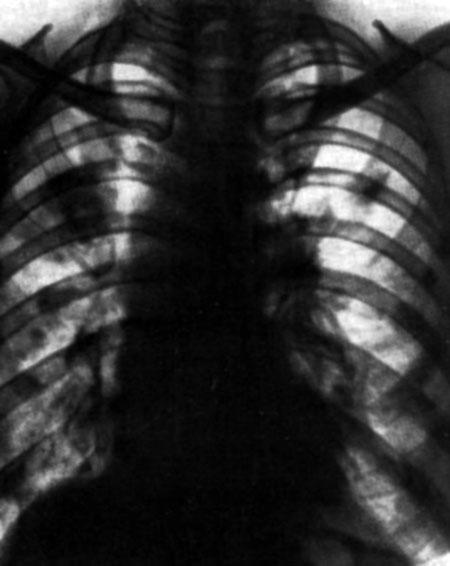

При аспергиллёзе лёгких могут развиться так называемые аспергиллёмы, представляющие собой опухолевидное образование — шарообразный конгломерат состоящий из мицелия гриба и клеточного детрита, находящийся в хронической легочной полости[11].

Появляется кашель с выделением зеленоватой гнойной мокроты, кровохарканье. В мокроте обнаруживают нити и споры гриба в виде серовато-зеленоватых хлопьев. При рентгенологическом обследовании выявляются инфильтраты, полости. При аспергиллёзном бронхите наблюдается отёк слизистой, возникают гнойные и лимфоцитарные инфильтраты. При аспергиллёзной пневмонии гифы гриба прорастают ткань лёгкого[12].

Злокачественной смертельной формой аспергиллёза лёгких является так называемый инвазивный аспергиллёз лёгких[13]. С аспергиллёзом лёгких не следует смешивать алеллргию на грибов рода Aspergillus, которая обуславливает аллергический бронхолегочный аспергиллёз[14].